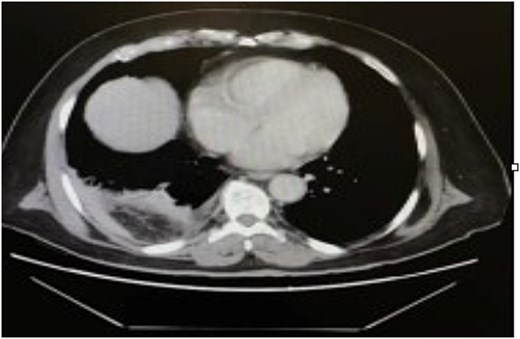

The patient was initially resuscitated with intravenous fluids. An urgent abdominal computed tomography (CT) scan was performed, revealing a herniated and obstructed segment of large bowel loops with mesenteric fat at the hepatic flexure, likely through the posterior right hemidiaphragm (Fig. 1). The scan showed a proximally dilated cecum and ascending colon, with a transitional zone observed at the neck of the hernia, leading to a distally collapsed colon. Additionally, there was an area suspicious for pneumatosis intestinalis within the obstructed bowel segment, along with adjacent fat stranding and free fluid—findings that raised concerns for strangulation or early ischemia. The scan also indicated a right-sided pleural effusion and adjacent atelectasis (Fig. 2).

CT scan of the thorax revealed a right-sided pleural effusion and adjacent atelectasis.